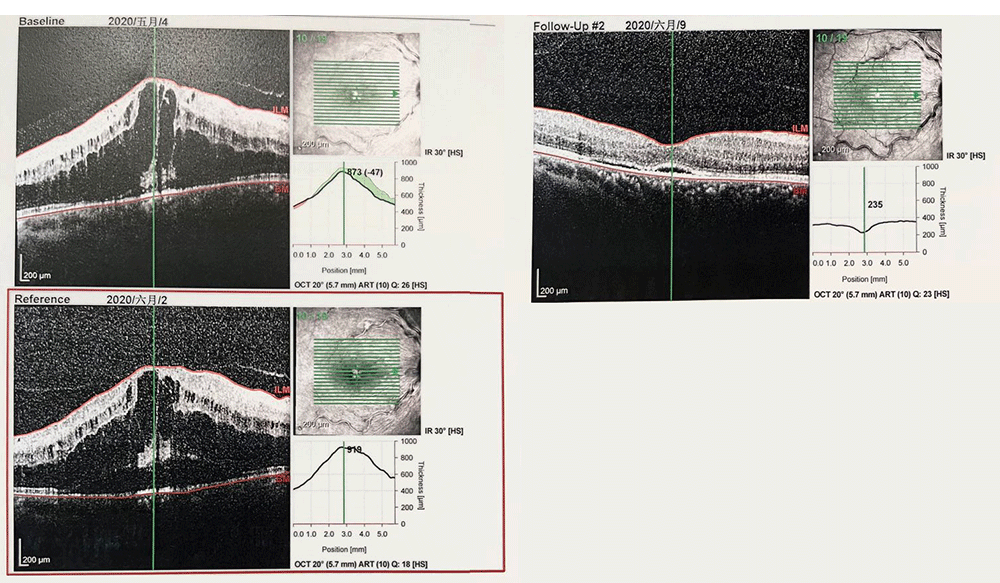

第2次抗VEGF治疗后25天,2020年5月4日

视力下降

视力:VOD 0.2

眼压:14mmHg

行右眼第3次抗VEGF治疗(雷珠单抗)

雷珠单抗10次注射CRT趋势

2020.2.6-11.24共注射雷珠单抗10针,每次注射后CRT均有不同程度消退,但每次25天左右即复发至800-1000um,视力则在小数视力0.8-0.1之间波动,末次随访视力为0.2。

整体趋势来看患者CRVO-ME治疗效果在下降